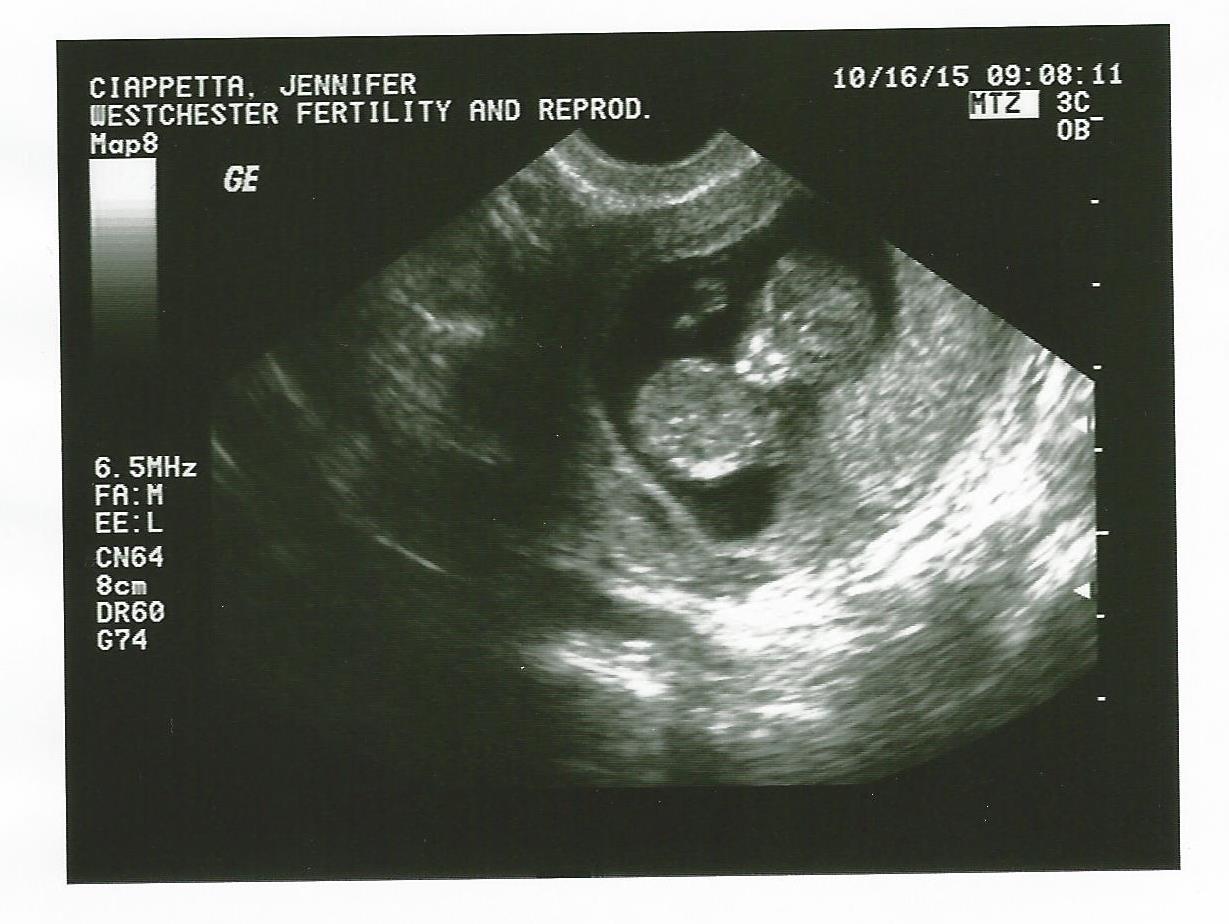

8 week ultrasound and there's twins! We were only able to see one heart beat and they thought I'm a week behind where I thought I was so please send good growing thoughts my way. Headed back in a week to hear Baby B. also if anyone has had experience in this area, please advise.</p>